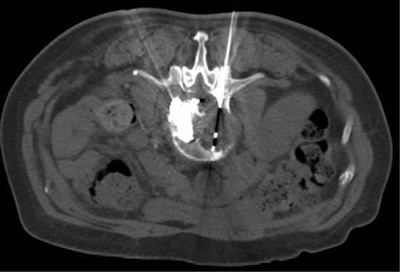

![]() | ![]() |

| (肺癌的介入治疗) | (盆腔恶性肿瘤的介入治疗) |